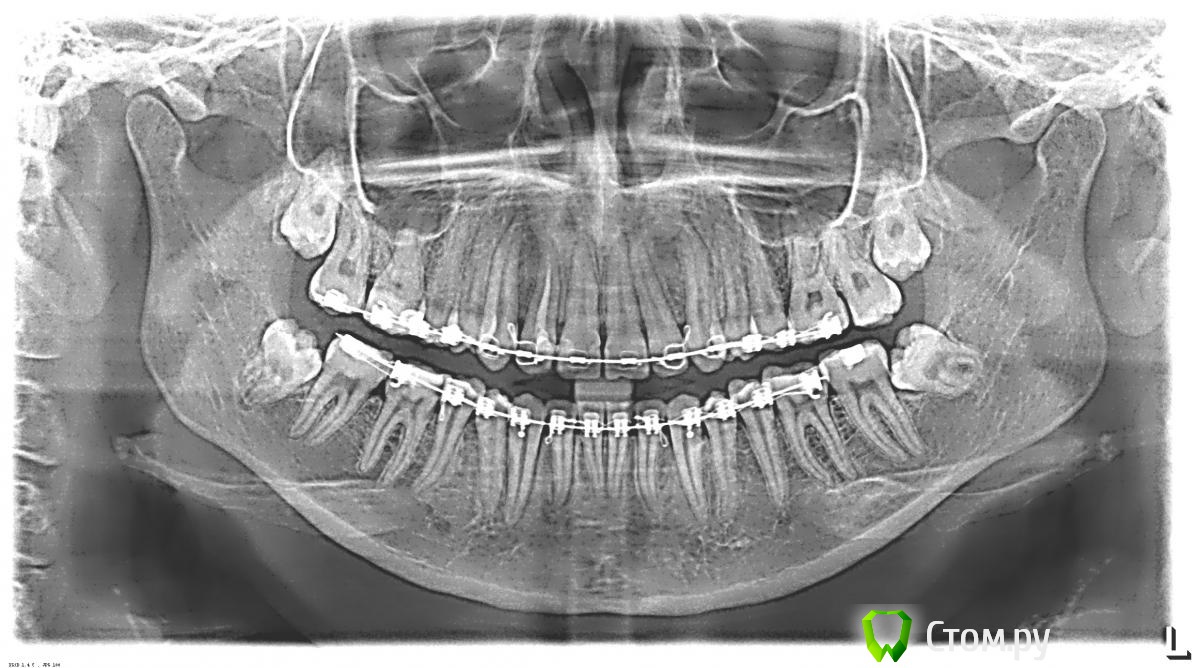

Milano0 Опубликовано 13 марта, 2014 Поделиться Опубликовано 13 марта, 2014 Здравствуйте!мне ортодонт назначил удаление всех восьмерок.посоветуйте пожалуйста хирурга в Москве,очень хочеться попасть к хорошему специалисту...еще вот думаю удалять под общим наркозом,есть ли разница,как лучше местный или общий?и хотелось бы еще узнать насколько сложный у меня случай? Ссылка на комментарий

red_butler Опубликовано 13 марта, 2014 Поделиться Опубликовано 13 марта, 2014 Спасибо) А вы еще не подскажите,всё же очень сложный случай у меня или нет?я не паникёр,просто люблю готовить себя заранее))В правильных руках не самый сложный, можно удалить все сразу. В идеале под седацией 1 Ссылка на комментарий

IvanK Опубликовано 13 марта, 2014 Поделиться Опубликовано 13 марта, 2014 Либо в 2 этапа:право и лево+1. Сложностей в правильных руках нет 1 Ссылка на комментарий